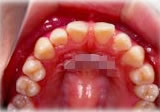

反対咬合(受け口)症例

初診時年齢24歳6ヶ月。前歯部反対咬合を主訴に来院。

骨格性反対咬合と診断し、外科的処置を併用して治療。

上顎 上顎 上顎